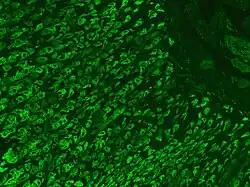

The presence of antibodies to gastric parietal cells and intrinsic factor is common in PA. Parietal cell antibodies are found in other autoimmune disorders and also in up to 10% of healthy individuals. However, around 85% of PA patients have parietal cell antibodies, which means they are a sensitive marker for the disease. Intrinsic factor antibodies are much less sensitive than parietal cell antibodies, but they are much more specific. They are found in about half of PA patients and are very rarely found in other disorders. These antibody tests can distinguish between PA and food-B12 malabsorption.[57][58]